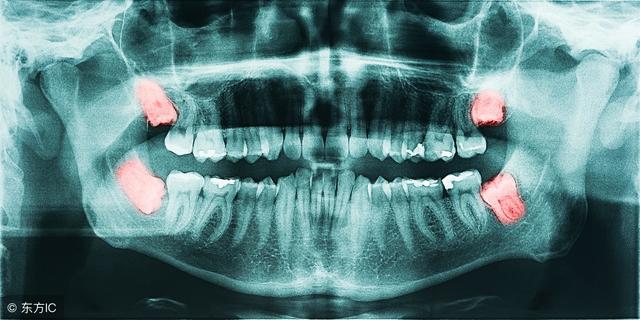

智齿就是口腔中的最后面的臼齿,有人会长,有人终生都不会长。不少人体验过智齿犯了,会疼的要命。

1. 影响正常咬合。阻生智齿的生长位置是不足的,也没有对应对颌牙齿,使之不能建立正常的咬合关系,长时间就会导致张口疼痛、磨牙等症状,对青壮年的身心影响较大。

4. 邻牙拥挤和松动。由于智齿的长歪没有足够的空间生长,就会挤压到相邻的牙齿,使相邻的牙齿松动,产生牙痛出血等症状。